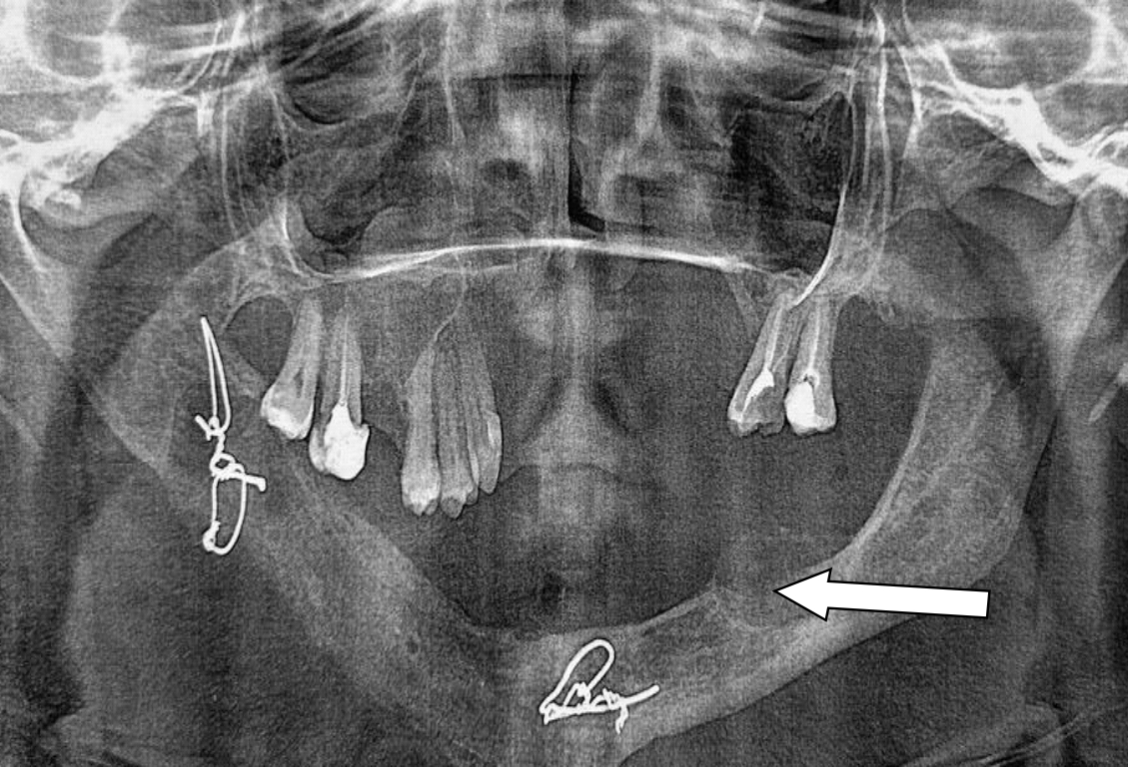

On the control orthopantomogram, an implant is fixed in the area of the defect of the lower jaw on the right, the fixation is satisfactory. The shadows of metal-density ligature sutures are visible in the area of the right lower jaw branch and the chin section of the lower jaw (Fig. 3).

Fig. 3. Orthopantomogram, condition six months after surgery (removal of osteoclastoma of the lower jaw in the body area on the right with simultaneous replacement of the defect with an orthotopic carbon implant "Uglekon-M")

Six months after the surgery, a removable dental prosthesis with a metal base and clasp fixation was made and fixed to the patient's lower jaw. The patient had no complaints and did not attend examinations as part of the dispensary observation due to her residence in a remote area of the Perm Territory.